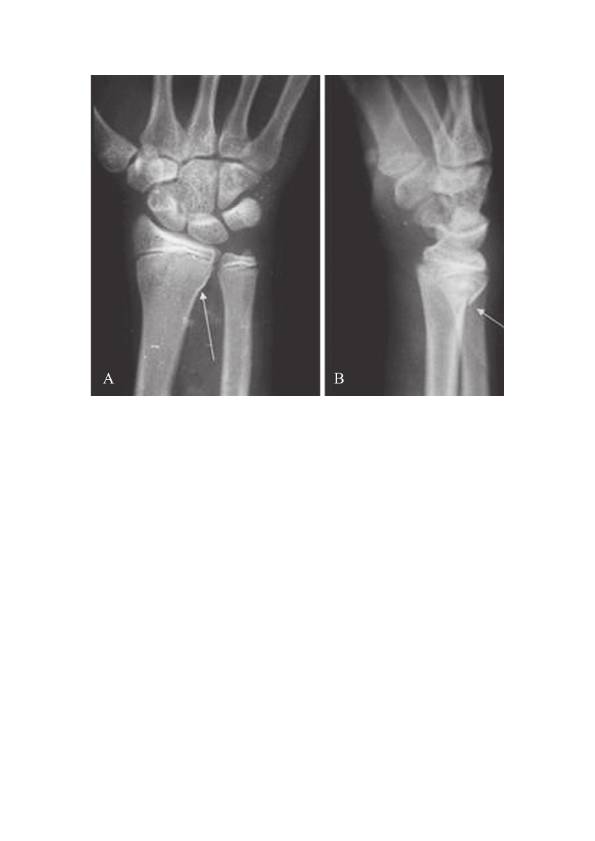

桡骨远端骨折